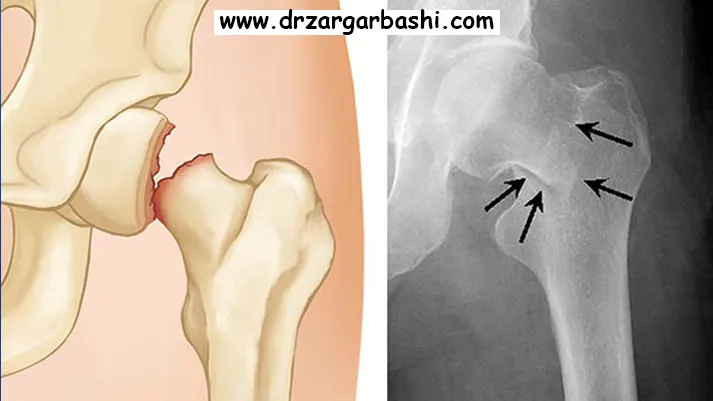

تشخیص شکستگی لگن در کودکان

برای تشخیص شکستگی لگن در کودکان، چندین نشانه و علامت وجود دارد که ممکن است کمک کننده باشد:

در هر صورت، برای تشخیص صحیح شکستگی لگن در کودکان، لازم است به پزشک متخصص مراجعه کنید. او میتواند با استفاده از امکانات تشخیصی مانند اشعه ایکس و تاریخچه بالینی کودک، به تشخیص درست برسد و درمان مناسبی را تجویز کند.